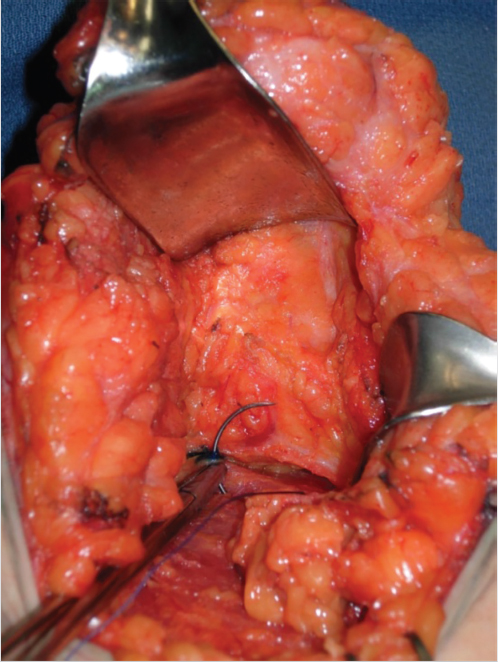

Parenchymal suturing—performed in almost every case. This includes pedicle fixation by “pexy sutures” to pectoralis major muscle fascia, suturing de-epithelialized dermal wings, and lower breast pillar sutures in case of vertical mastopexy (Fig. 31‑6).